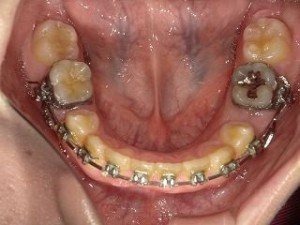

正面からの写真です。丸くひっかけるホックのようなものがあるのがわかるでしょうか?

わかりにくいですが下のほうにも同じ引っ掛けるところがあります

それが顎間ゴムを引っ掛けて歯を牽引する役割を担っています

そして今回も前回の写真と比較してみます。

下顎がものすごく幅が縮まっているのがわかります。これはすごい。